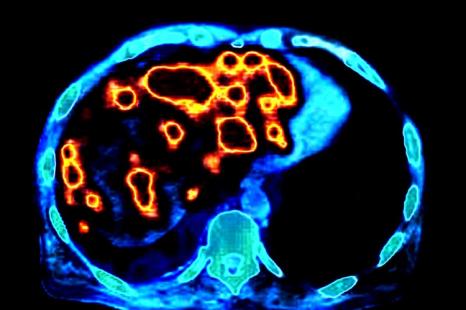

Crédit photo : PHANIE